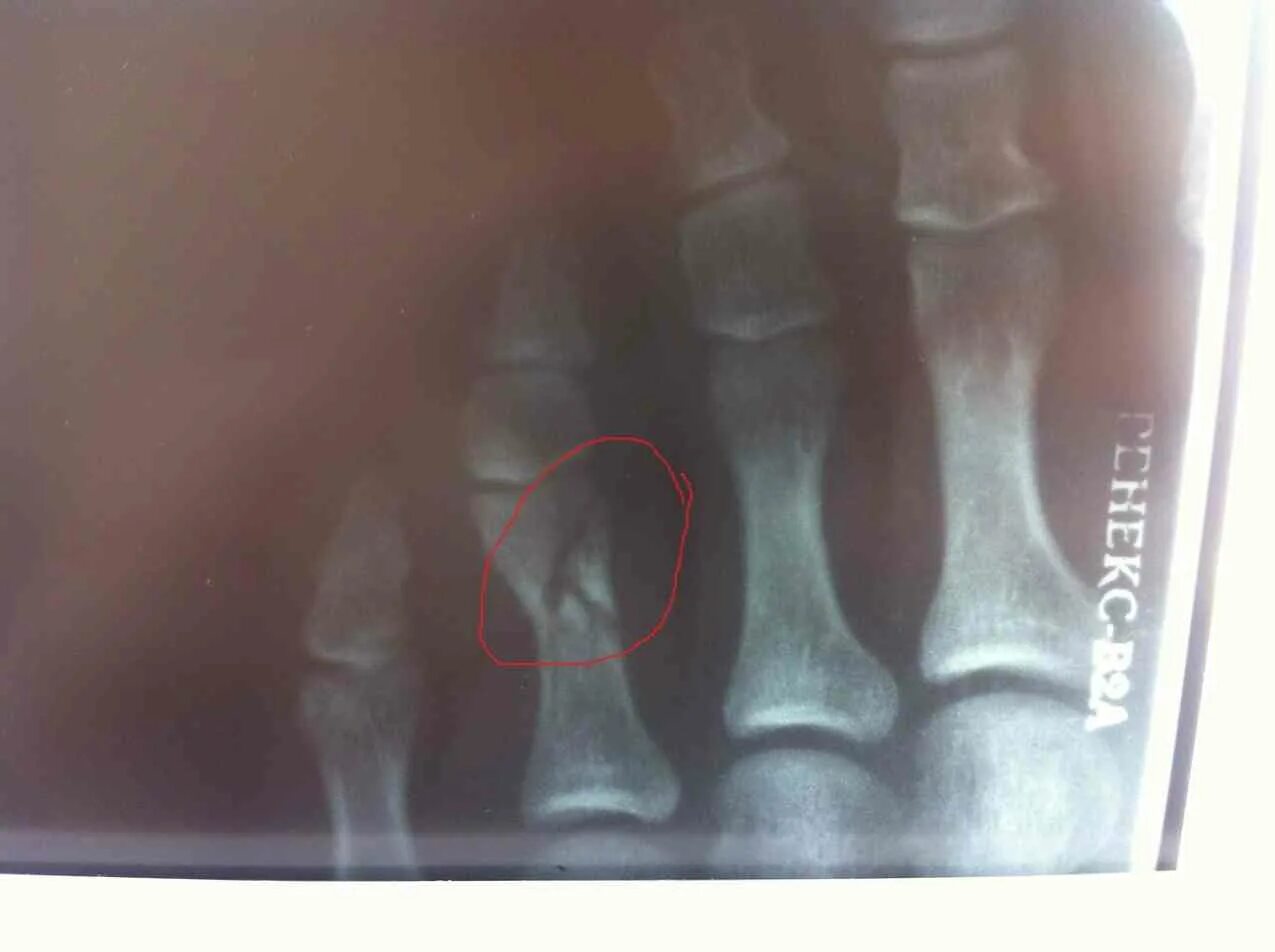

Закрытый перелом пальцев стопы мкб 10